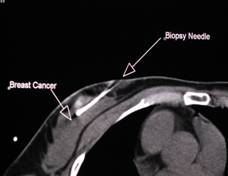

STEP 4: CAT

scan

This step was taken solely for the

benefit of those individuals who would try to discredit this

technology. NCIT's founder, Robert Dowling, wanted to

prove that the mass was, in fact, cancer -- and, of course, it

was. With QHM®

technology, a biopsy is no longer necessary. A

"guiding" CAT scan is used for the proper placement of the

ablation device to kill the tumor. The CAT scan is a second

proof of the cancer.